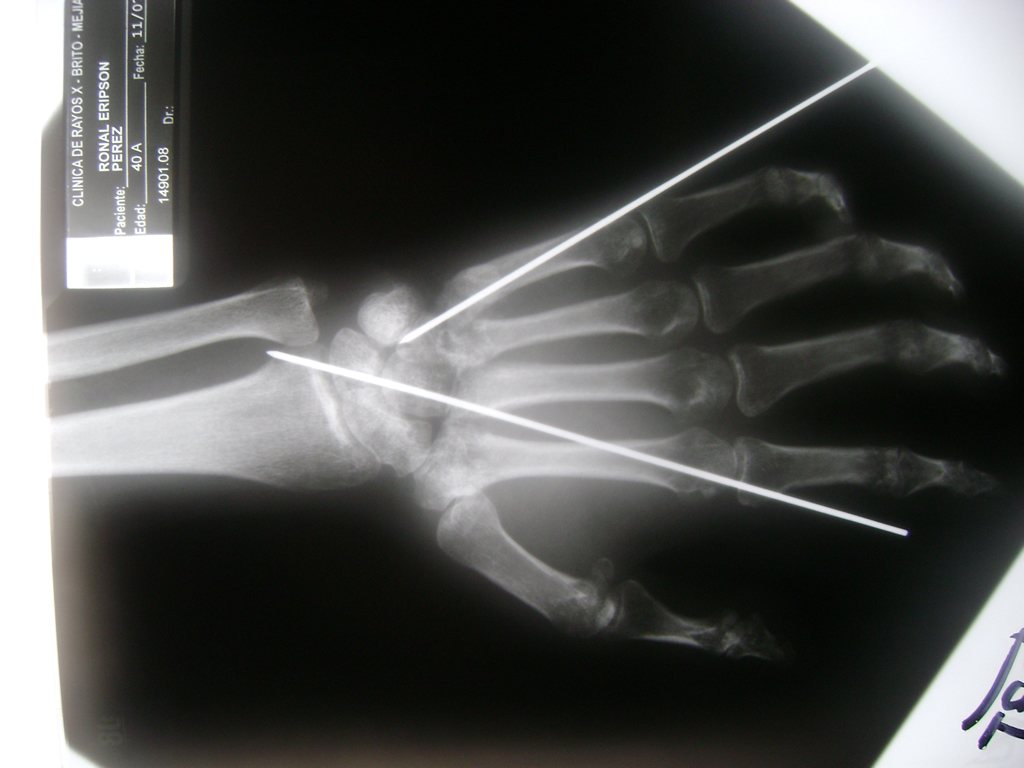

Cirugía de Muñeca y Mano

Los procedimientos más comunes en cirugía de la mano son aquellos destinados a reparar traumatismos, incluyendo lesiones de tendones, nervios, vasos sanguíneos, y articulaciones; huesos fracturados; y quemaduras, cortes, y otros daños de la piel.